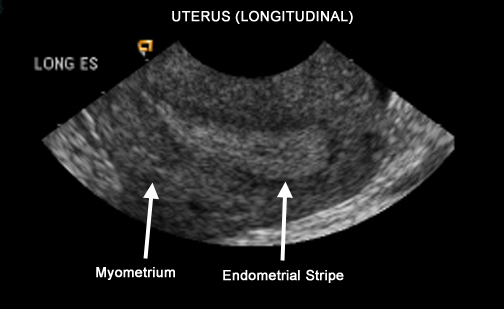

US Pelvis |